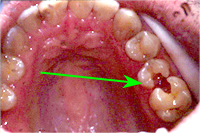

Abb. 1 zeigt das klinische Bild vor der Aufklappung. Der Pfeil markiert die Stelle, wo der Weisheitszahn unter der Schleimhaut im Knochen liegt. Vor der Operation musste ein CT zur transversalen Lagebeurteilung des sensiblen, wichtigen Lippennerves zur Wurzelspitze des Zahnes angefertigt werden. In der CT-Schichtaufnahme von Abb. 2 wird ersichtlich, dass der Weisheitszahn sehr tief unten liegt.